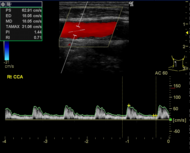

頸動脈エコー検査

頸動脈エコー検査(エコー検査は省略可です)